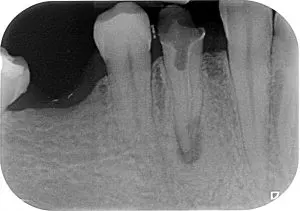

Rzeszów. Idę do umówionego i znanego już mi z wcześniejszych wizyt gabinetu stomatologicznego. Siadam, w skrócie opowiadam o co chodzi, ściągamy opatrunek, robimy kolejne zdjęcie i pani dentystka trochę pesymistycznie stwierdza, że nie podejmie się w tym przypadku leczenia kanałowego, ponieważ dojście do korzeni jest wyjątkowo niekorzystne i trzeba będzie to zrobić przy pomocy mikroskopu… ,,Hmmm…, no świetnie” -pomyślałem. Miało być gładko i przyjemnie a nie jest. Cóż począć? Miła pani stomatolog proponuje, aby podzwonić, poszukać jakiegoś innego gabinetu, w którym daliby radę uporać się z zaistniałą sytuacją. Brzmi rozsądnie, lecz jest jedno ,,ale”, które może być nie do przeskoczenia… Brak czasu. Mam tylko parę dni do powrotu i całkiem prawdopodobne, że może nie być wolnych terminów. Gdyby tak się stało, to mam wrócić, zamknie się na powrót zęba opatrunkiem i podczas kolejnej wizyty w Polsce się to zrobi. Zgadzam się na to co powyżej, zakładamy opatrunek i do działania!

Gabinet obszerny, jasny, z dużym biurkiem i nowoczesną aparaturą dentystyczną. Sekunda i już siedzę w najważniejszym miejscu pomieszczenia. Po krótkiej rozmowie informacyjne drobna pani dentystka zaczyna działać. Pierwsza rzecz to znieczulenie i od razu zaskoczenie: nie ma igły, nie ma ukłucia, nie ma krwi a jest znieczulenie komputerowe! Bezstresowo i bezboleśnie a to najważniejsze, w parę sekund dziąsło bez czucia. Rozłożywszy się w fotelu i przyjąwszy pozycję leżącą, otworzyłem szeroko usta i czekałem. Wiertło grube, wiertło cienkie, rurka odsysająca ślinę, wacik ją wchłaniający. Leżę i zerkam: na okno, na ściany, na aparaturę wszelaką, na twarz pani dentystki, na moje buty i na przemieszczającą się tu i ówdzie asystentkę. Wkładają mi do ust jakieś żelastwo, podkręcają i montują na zęba. Umieszczają gumową szmateczkę, tak że widoczna jest tylko naprawiana czwórka. Skupiona pani doktor patrzy w mikroskop, następnie na ekran komputera, jednocześnie wykonując znane tylko sobie czynności. Ja leże i mogę sobie tylko wyobrażać cóż tam się w mojej buzi misternego wyrabia. Następuje seria ucisków i przetykań ale nic nie boli – magia komputerowego znieczulenia działa. Pomaga sobie jak gdyby lutownicą, coś tam przypala bo unosi się dymek (w tym momencie czuję delikatne pobolewanie).